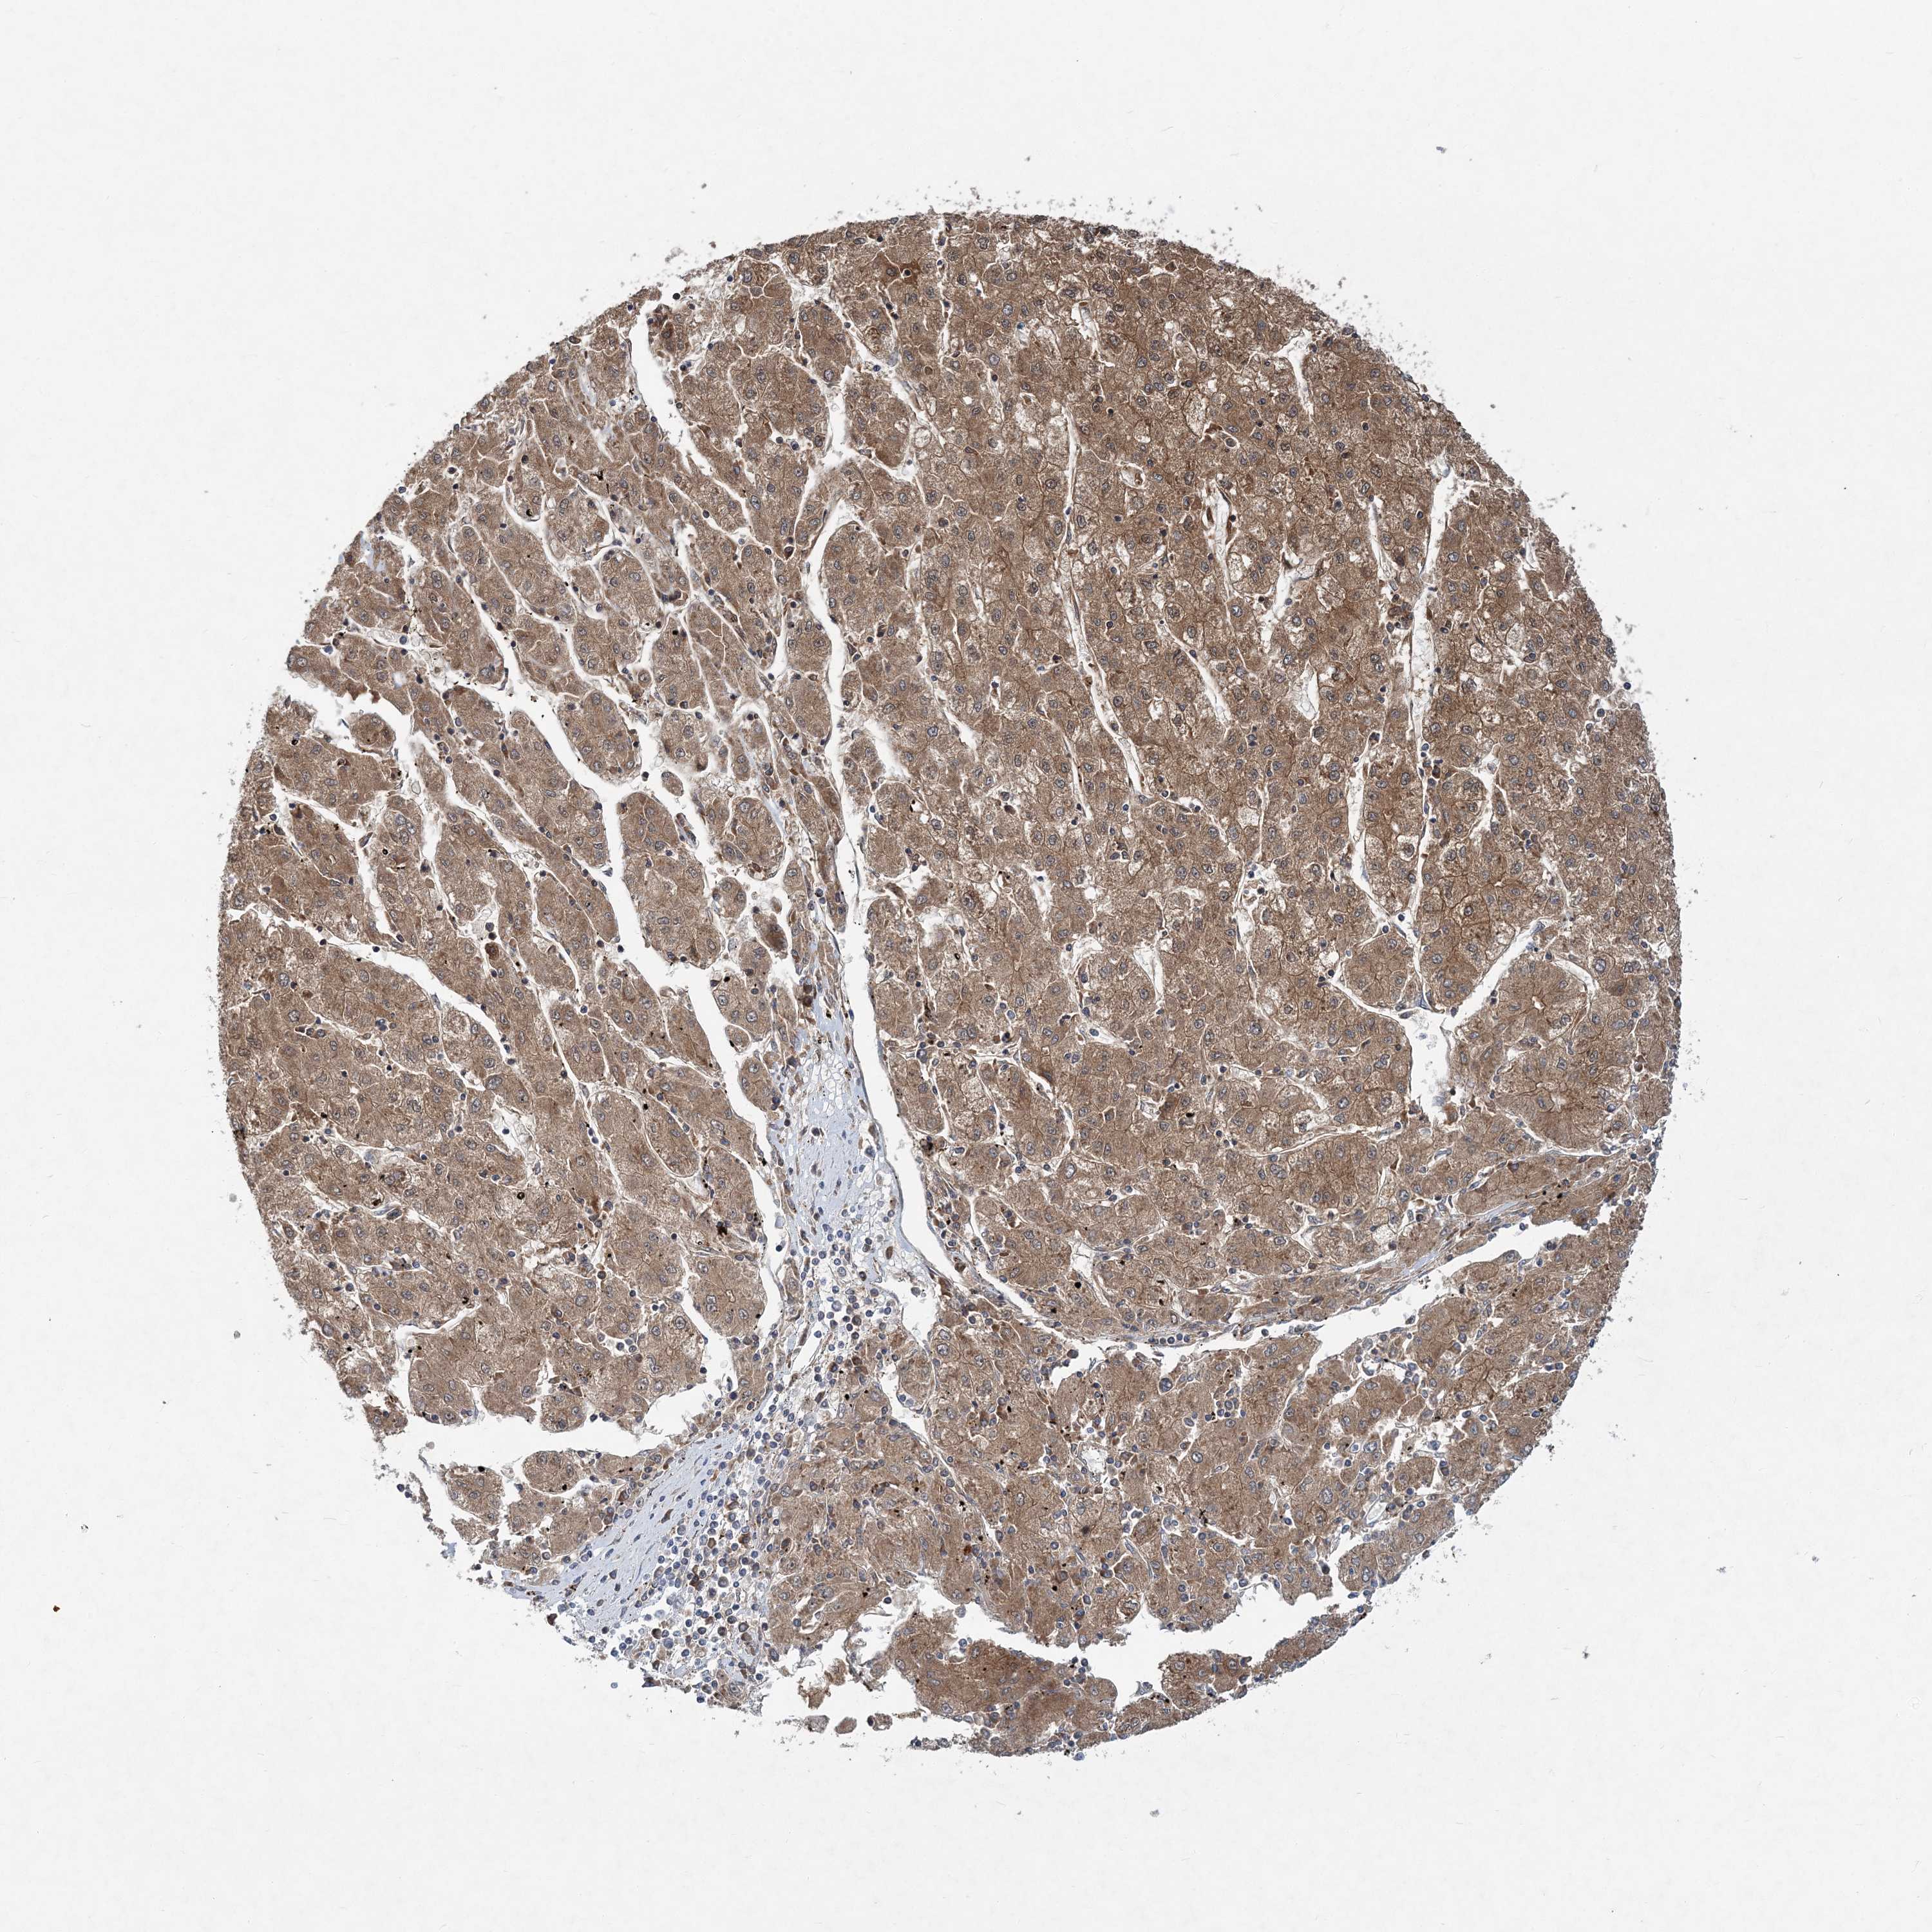

LIVER CANCER - Protein expressioni

A mouse-over function shows sample information and annotation data. Click on an image to view it in a full screen mode. Samples can be filtered based on level of antibody staining by selecting one or several of the following categories: high, medium, low and not detected. The assay and annotation is described here.

Note that samples used for immunohistochemistry by the Human Protein Atlas do not correspond to samples in the TCGA dataset.

Antibody stainingi

Antibody staining in the annotated cell types in the current human tissue is reported as not detected, low, medium, or high, based on conventional immunohistochemistry profiling in selected tissues. This score is based on the combination of the staining intensity and fraction of stained cells.

Each image is clickable and will lead to virtual microscopy that enables deeper exploration of all samples and also displays staining intensity scores, fraction scores and subcellular localization as well as patient and tissue information for each sample.

Antibody HPA036817

Staining

High

Medium

Low

Not detected

Intensity

Strong

Moderate

Weak

Negative

Quantity

>75%

75%-25%

<25%

None

Location

Nuclear

Cytoplasmic/membranous

Cytoplasmic/membranous,nuclear

Cholangiocarcinoma

Carcinoma, Hepatocellular, NOS